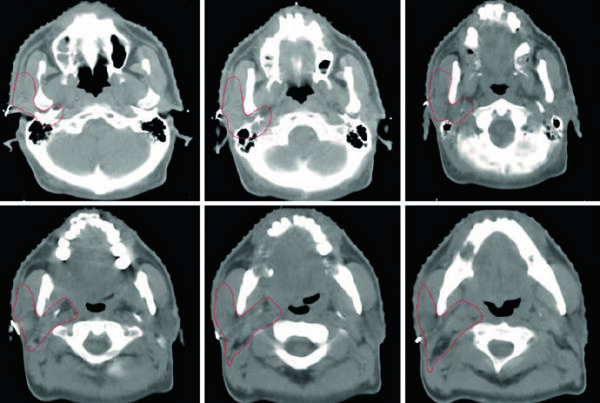

Comparação entre Algoritmos na Prática Clínica

A diferença entre algoritmos se manifesta mais claramente em condições desafiadoras: campos pequenos, feixes de alta energia e heterogeneidades acentuadas — especialmente pulmão. A figura ao lado ilustra isso de forma dramática: para um feixe de 15 MV, campo 2,8×14 cm, 4 cm off-axis, atravessando 10 cm de pulmão (ρ = 0,2 g/cm³), as curvas de dose em profundidade divergem significativamente entre os algoritmos.

Monte Carlo ($MC_w$) serve como referência. O Collapsed Cone (CC-TMS, CC-PIN) acompanha razoavelmente bem, com desvios moderados na interface e dentro do pulmão. O AAA (AAA-ECL) segue de perto o CCC mas com desvios na interface tecido-pulmão. Já o Pencil Beam (PB-TMS, PBC-ECL) superestima a dose dentro do pulmão por uma margem clinicamente significativa e não consegue reproduzir a redução de dose lateral causada pela falta de equilíbrio eletrônico.

Na prática clínica, a escolha do algoritmo deve considerar o sítio anatômico e o cenário clínico. Para planejamentos em abdome, pelve ou cabeça e pescoço — onde as heterogeneidades são menos dramáticas — mesmo um pencil beam pode ser aceitável para planejamento forward, embora um algoritmo tipo “b” seja sempre preferível. Para pulmão, mama com campo tangencial passando por pulmão, mediastino, ou qualquer situação com campos pequenos de alta energia, um algoritmo tipo “b” (CCC, AAA, Monte Carlo ou Acuros) é essencial e não-negociável.